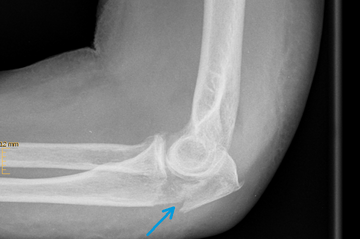

Ellenbogenfrakturen

Das Ellenbogengelenk besteht aus den beiden Unterarmknochen Elle (Ulna) und Speiche (Radius) sowie dem unteren Anteil des Oberarmknochens (Humerus).

Häufig müssen Frakturen des Ellenbogengelenkes operiert werden, da bereits kleinere Verschiebungen der Gelenkflächen zu einem schnellen Verschleiß und einer Funktionsminderung des Gelenkes führen.

Ellenhakenbruch (Olekranonfraktur)

Das Olekranon ist das ellenbogenseitige Ende der Elle (Ulna). Hier befestigt sich die Sehne des Unterarmstreckers (Trizepsmuskel) und überträgt so die Kraft der Streckmuskulatur auf das Olekranon und den Unterarm.

Frakturen des Olekranons sind häufig, sie können einfach aber auch sehr komplex sein.

Ein stabiler Ellenbogenbruch (Olekranonfraktur), bei dem die Bruchstücke nur minimal voneinander entfernt liegen und keine Verschiebung aufweisen, kann nicht operativ (konservativ) behandelt werden. In diesem Fall wird der betroffene Arm im Gips oder in einer Orthese ruhig gestellt.

Ist dieses nicht der Fall und es liegt eine komplexe Fraktur mit verschobenen Knochenfragmenten vor, erfolgt in der Regel eine Operation. Durch den Zug der Streckmuskulatur klaffen die einzelnen Bruchstücke weit auseinander. Zur Fixierung der Fraktur und Wiederherstellung der Gelenkfunktion ist eine Verdrahtung oder Verplattung des Bruchs notwendig.